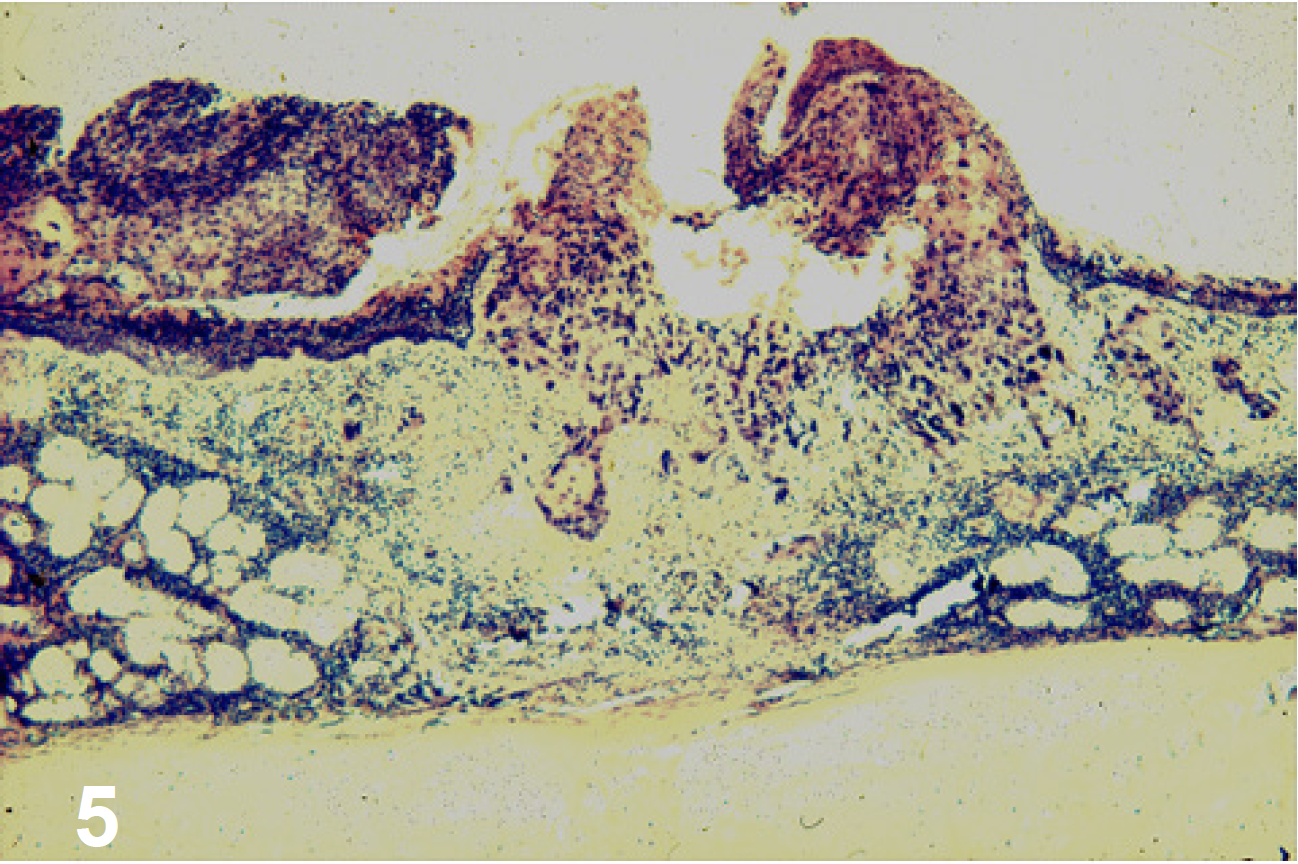

Histología

CPCNP [figura 5].